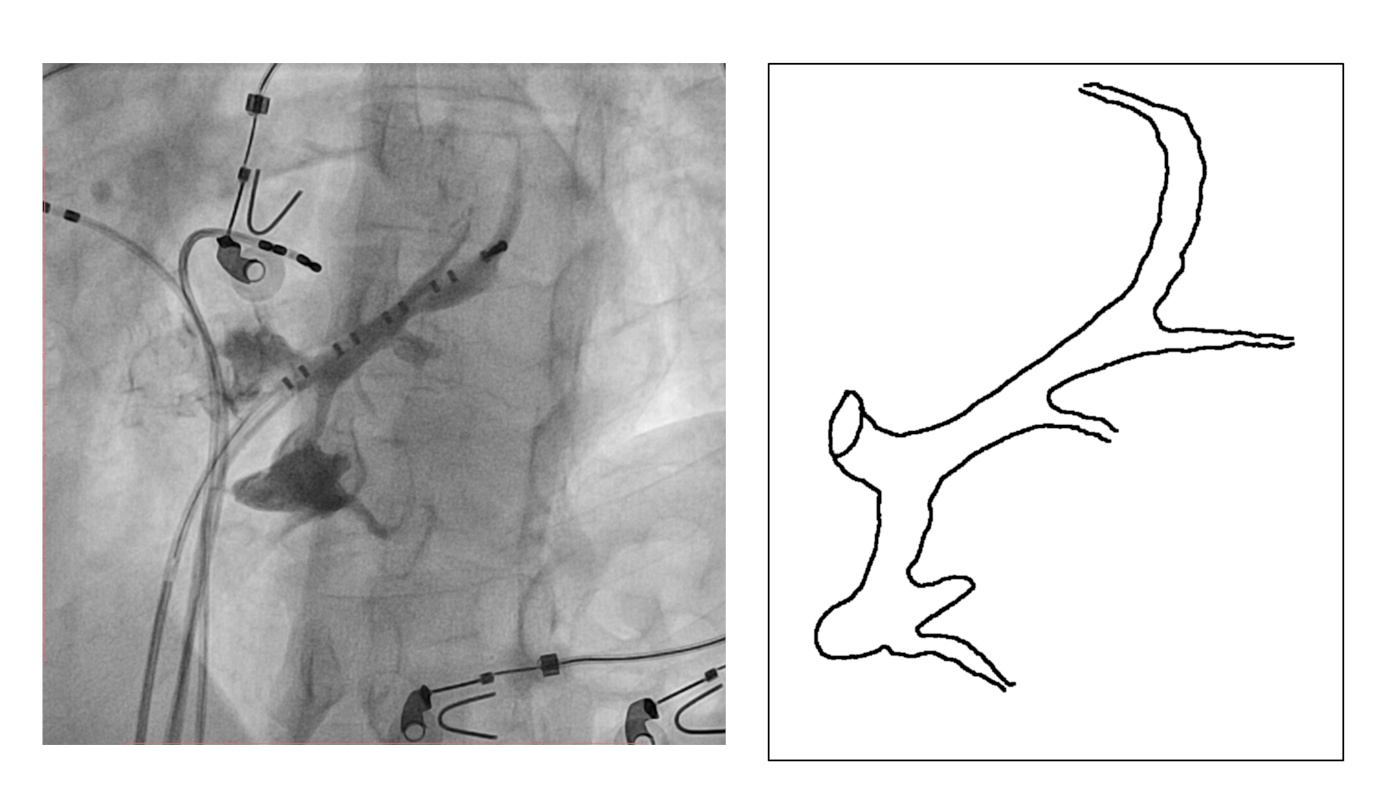

CS diverticulum

ecg.jpg

Mapping in diverticulum

diverticulum.jpg

med_lat_div.jpg

signals.jpg

Mapping in diverticulum - CSE potential most important

div_schematic.jpg

Selvaraj RJ et al. Radiofrequency ablation of posteroseptal accessory pathways associated with coronary sinus diverticula. J Interv Card Electrophysiol. 2016 Nov;47(2):253-259. doi: 10.1007/s10840-016-0113-x.